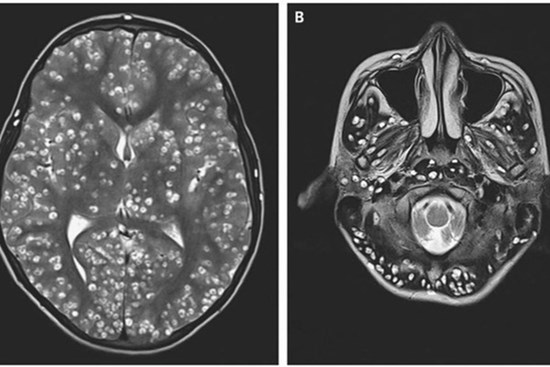

Bác sĩ phát hiện 700 con sán dây "làm tổ", gây tổn thương trong não, ngực và phổi của một người đàn ông ăn thịt lợn chưa chín

Người đàn ông này kể lại rằng ông bắt đầu bị đau đầu và co giật sau khi ăn lẩu nhưng phải đến 1 tháng sau ông mới đến khám.